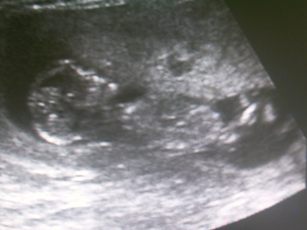

ultrahang 12.hét